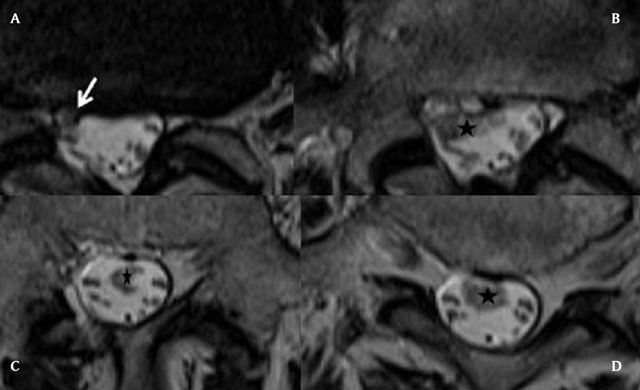

Figure 3A–D

Axial T2 slices of the lumbar spine, from the level of the L4-L5 disk to the sacrum. The IDH enters at the L4-L5 level (white arrow) and extends downwards in the CSF, to the L5-S1 level (black stars). It has irregular borders, heterogeneous nodular structure and variable diameter.